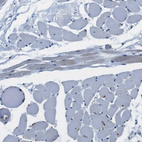

Immunohistochemistry analysis in human spleen and skeletal muscle tissues using HPA015663 antibody. Corresponding CD163L1 RNA-seq data are presented for the same tissues.